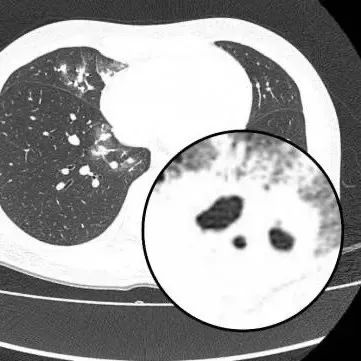

该科室刘知陶主任查房时,敏锐捕捉到CT上形似“鬼脸”的特殊影像(即“鬼脸征”),并伴有“晕伦征”,高度怀疑隐球菌肺炎。医生追问夏女士近期是否曾接触鸟类、禽类及饲养宠物,夏女士否认。

在影像学表现方面,典型CT表现是单发/多发结节伴“晕轮征”,结节液化坏死可形成空洞形似“鬼脸征”,空洞常为薄壁空洞、无液平。